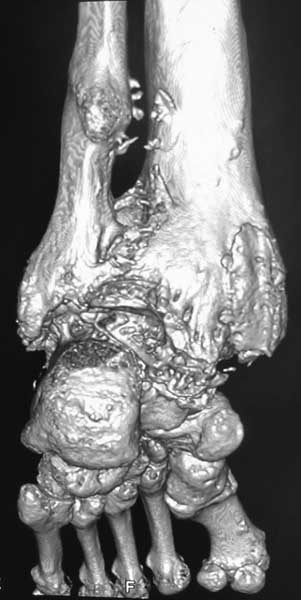

У пациентки резко выраженная вальгусная деформация стопы. При попытке выполнения артродеза без коррекции оси конечности вероятность несостоятельности артродеза и сохранения болей крайне велика. Артроз имеет односторонний характер и связан, с большой степенью вероятности, с нарушением оси конечности. При восстановлении правильной оси такой сустав сможет послужить еще не один год. В плане дообследования обязательны снимки в переднезадней проекции под нагрузкой с захватом бугра пяточной кости, которые помогут лучше оценить осевые взаимоотношения голени и стопы. Исправить эти взаимоотношения можно, как путем медиализирующей остеотомии пяточной кости, так и путем остеотомии большеберцовой кости. Сохраняющая голеностопный сустав хирургия сейчас на подъеме, ей посвящаются симпозиумы, статьи. Она служит, как для сохранения сустава, так и для подготовки последующих успешных операций артродезирования или протезирования.

Во вложении - пример операции при гораздо более грубом посттравматическом артрозе, позволившей пациенту 61 г. через 1.5 г. после корригирующей остеотомии не думать о следующем вмешательстве. Хотя, есть работы, показывающие, что максимальный эффект после подобных остеотомий развивается к двум годам.

Красиво конечно, но верится с трудом , что с таким артрозом пациента перестали беспокоить боли и ограничение движений в суставе. Возможно я и ошибаюсь.

При чем тут ограничение движений когда речь идет об артродезе? Конечно ограничение осталось. А вот боли уменьшились на порядок. И стопа стала на место. Во всяком случае, сейчас вопрос об операции не стоит. А если встанет, то можно будет гораздо проще и с большей степенью вероятности получения положительного результата выполнить артродез. Но на самом деле артрозы голеностопного сустава при правильной оси конечности часто протекают очень благоприятно даже при далеко зашедших стадиях.